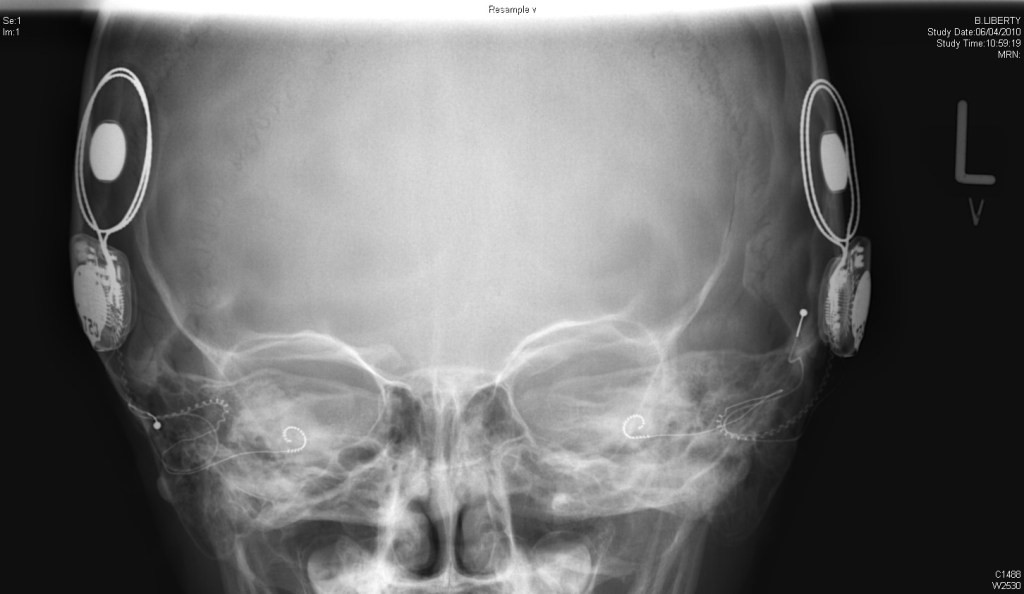

Chirurgia implantului cohlear

Implantul este plasat chirurgical în spatele urechii şi include:

Extern:

• Unul sau mai multemicrofoane pentru captarea sunetelor din mediul înconjurător;

• Unprocesor de sunete care filtrează selectiv sunetele, prioritizând sunetele legate de vorbire, împarte sunetele pe canale şi trimite semnalele electrice corespunzătoare printr-un fir catre transmițător;

• Untransmiţător, care este ţinut în poziţie de un magnet plasat în spatele urechii externe şi care transmite, prin piele (prin inducţie electromagnetică), putere electrică şi sunetele procesate, către partea internă a dispozitivului.

Intern:

• Unreceptor şi stimulator, fixat în os, sub piele, care converteşte semnalele primite de la transmiţător în impulsuri electrice şi le trimite printr-un cablu electric către electrozi;

• Oreţea de până la 22 de electrozi, împrăştiaţi pe cohlee, care trimit impulsuri către nervul vestibulo-cohlear.